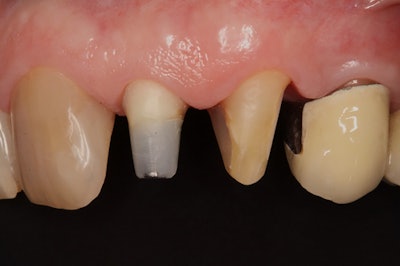

After the stabilization phase, final preparations were made for definitive restorations.